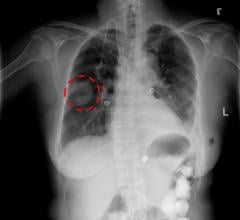

January 23, 2019 — An artificial intelligence (AI) system can interpret and prioritize abnormal chest X-rays with ...